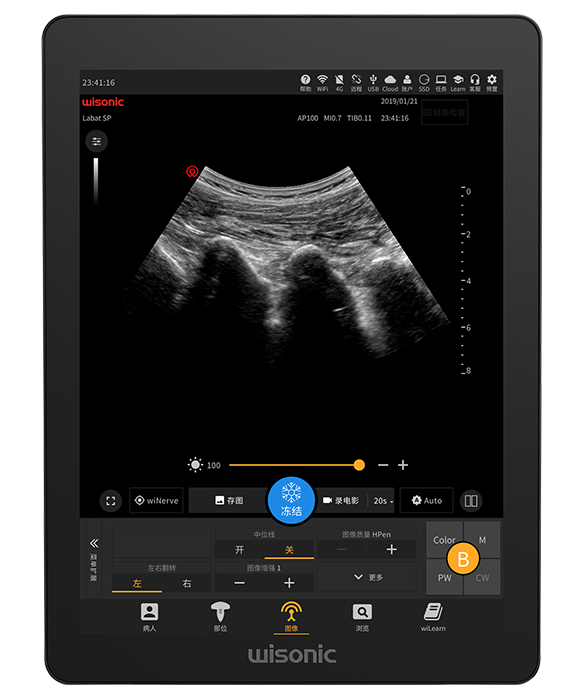

21.3 英寸超大尺寸全触摸显示屏

防炫、全尺寸、抗电刀、高灵敏度

极简控制面板

支持指纹识别、轨迹球精细调节等

超大的全触摸显示屏

支持液体消毒

多点触控

专为临床定制的极简面板

高灵敏度防水轨迹球

防泼洒

万向拨杆旋钮

产品图片